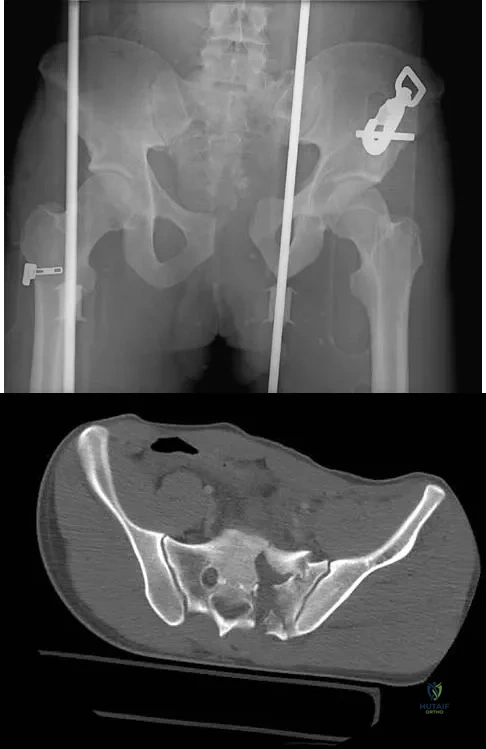

Question 34

A 40 year-old-man was involved in a motor vehicle accident and sustained the pelvic injury seen in Figures 24a and 24b. Definitive management of the injury should consist of reduction by

Explanation